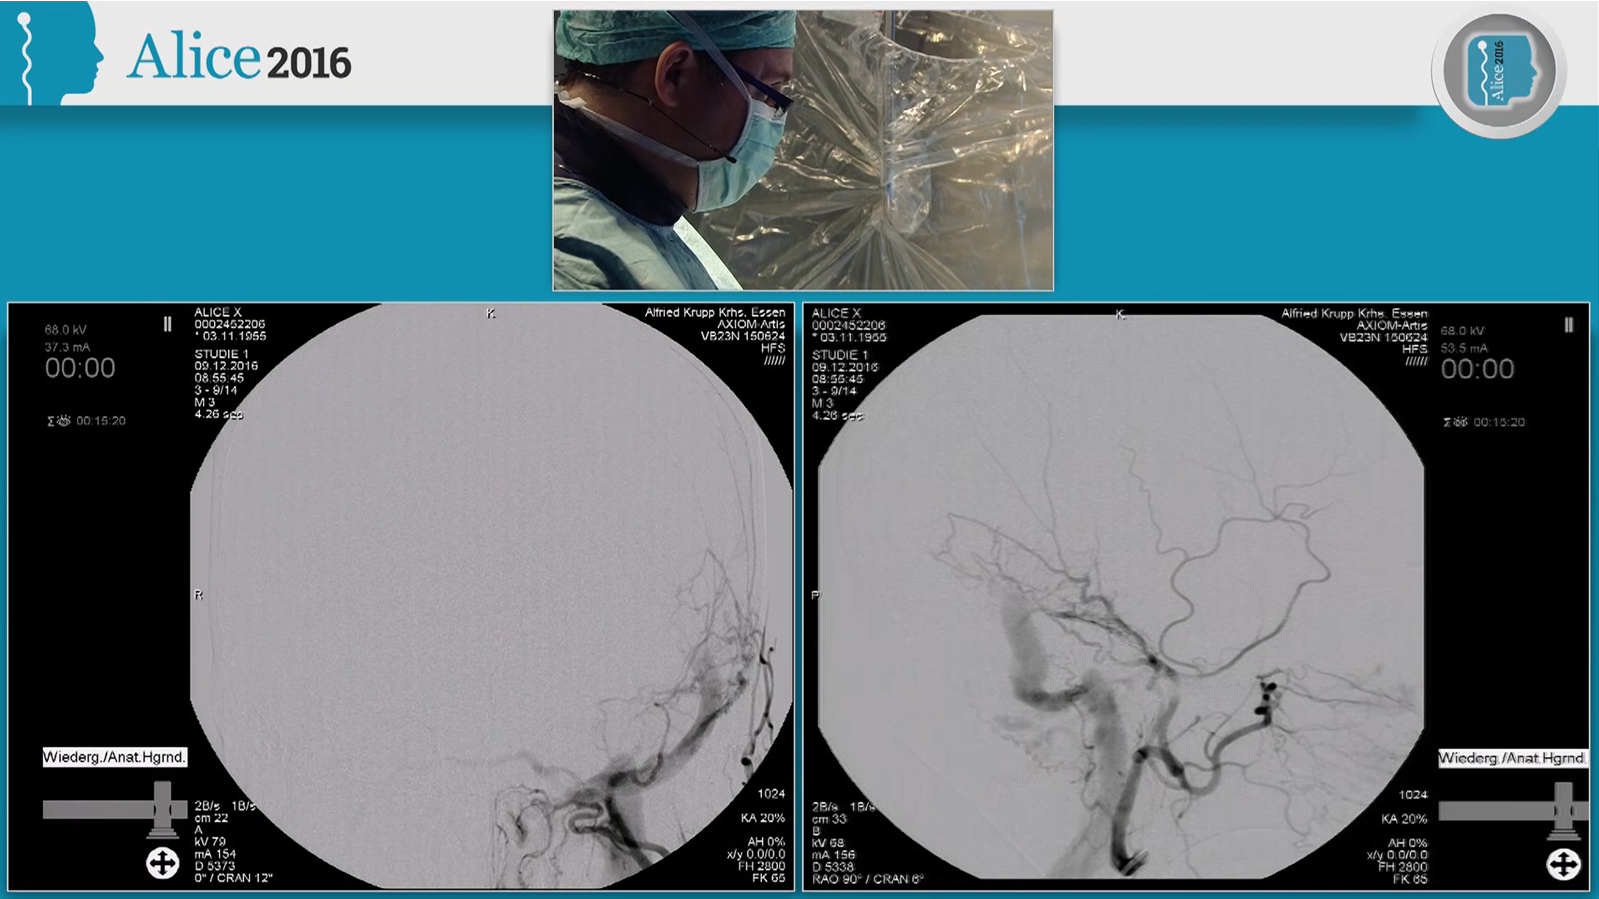

M1 occlusion, thrombectomy with Solitaire and balloon guiding catheter

M1 occlusion, thrombectomy with double Solitaire and balloon guiding catheter